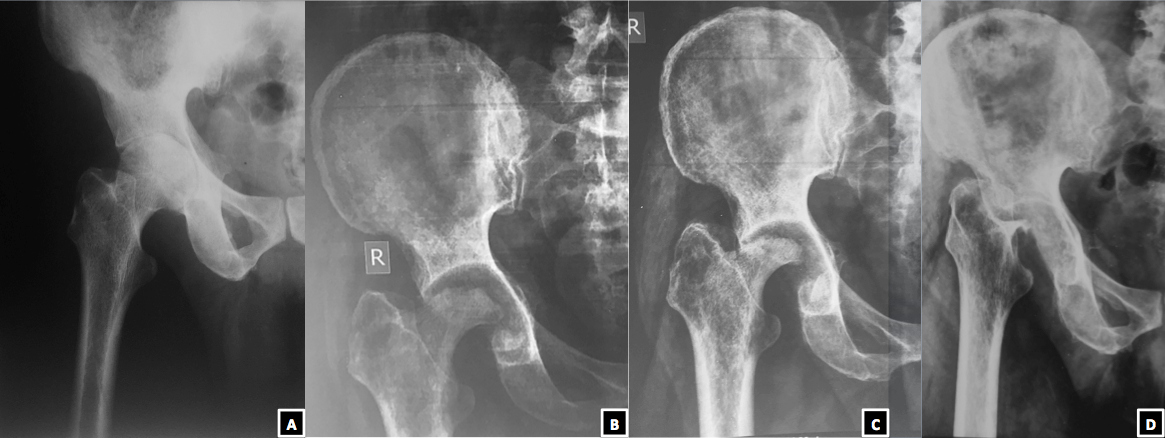

“Missing head sign”

A 56 years old male, farmer by occupation, presented with an altered gait. Five years back he had pain in right hip associated with fever and loss of body weight. On investigation, Erythrocyte Sedimentation Rate was raised (70 mm in first hour), X-ray revelaed dimunition of joint space and erosion of articular margins (A). On further investigation he was found to be mantoux test positive. Based on the clinicoradiological finding, he was started on Antitubercular Therapy (ATT). He was well counselled regarding the duration of treatment and the need of regular intake of drugs as prescribed from a nearby Directly Observed Treatment Short Course (DOTS) centre. After starting ATT, the fever subsided. The pain gradually settled. However, still he was having painless limp. He took ATT for 18 months as per our protocol. Two years later he followed up. X-ray revealed loss of major part of femoral head (B). The treatment options were discussed with the patient. As he was not having any problem in doing his activities of daily living, he did not opt for any surgical intervention rather went with a shoe raise option. A year further when he followed up, the X-rays revealed near complete loss of femoral head (C). At latest follow up, his x-rays showed that the femoral head was completely missing (D). We have given an acronym to this unusual presentation as a “Missing Head Sign”. As the patient was still managing his activities of daily living despite the limp, we have just kept him in regular follow up.